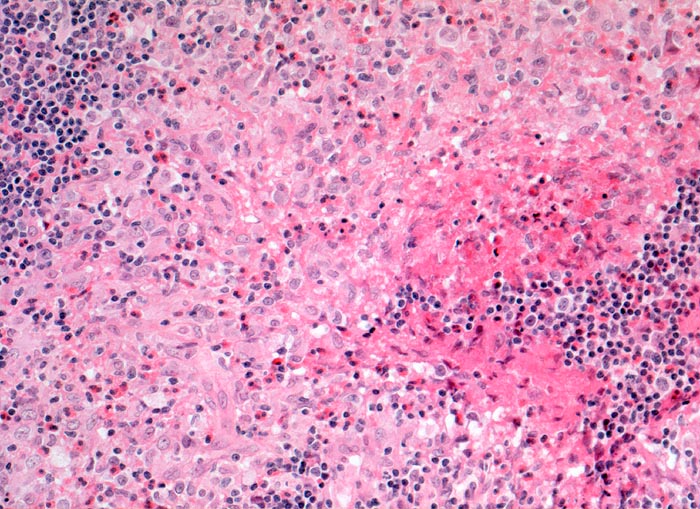

CD1a wird von einer Reihe von Antigen-präsentierenden Zellen exprimiert. Unter anderem Langerhanszellen und interdigitierende Reticulumzellen. 70% aller Thymozyten sind CD1a positiv, nicht aber frühe Thymozyten oder ausgereiften Thymozyten

Reaktion in Neoplasien:

Precursor T-ALL positiv. Post thymische T-CLL, Sezary Syndrom, kutanes T-Zell Lymphom und nodale T-Zell Lymphome negativ.

Diagnostischer Nutzen:

Identifikation einer Langerhanszellhistiozytose.

CD1a ist positiv in kortikalen Thymomen.